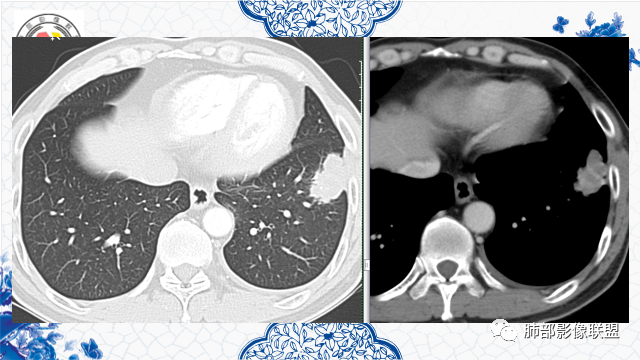

有胃肾恶性肿瘤手术史。左肺下叶胸膜下不规则肿块,部分边缘平直、部分膨隆,近端见支气管进入后截断,增强后不均匀强化,可见低密度坏死无强化,边缘见边界清楚的GGO,考虑恶性肿瘤——肺腺癌可能性大。鉴别转移瘤、鳞癌。

患者有胃肾肿瘤史,左肺下叶一不规则肿块,边界清晰,彭龙为主,靠近胸膜,有栽赃,支气管截断,内有坏死,考虑恶性腺癌可能。

发現肺占位3月,患者既往有肾、胃恶性肿瘤病史。胸部CT:左肺前外基底段近胸膜下不规则实性病灶,分叶,部分边缘平直、部分明显膨隆,内部密度不均匀,周围见磨玻璃影、边界清楚,支气管进入病灶堵塞,血管聚集,胸膜糊墙,增强扫描不均匀强化,内部多发低密度区。综合考虑恶性,转移?鉴别隐球菌、结核。